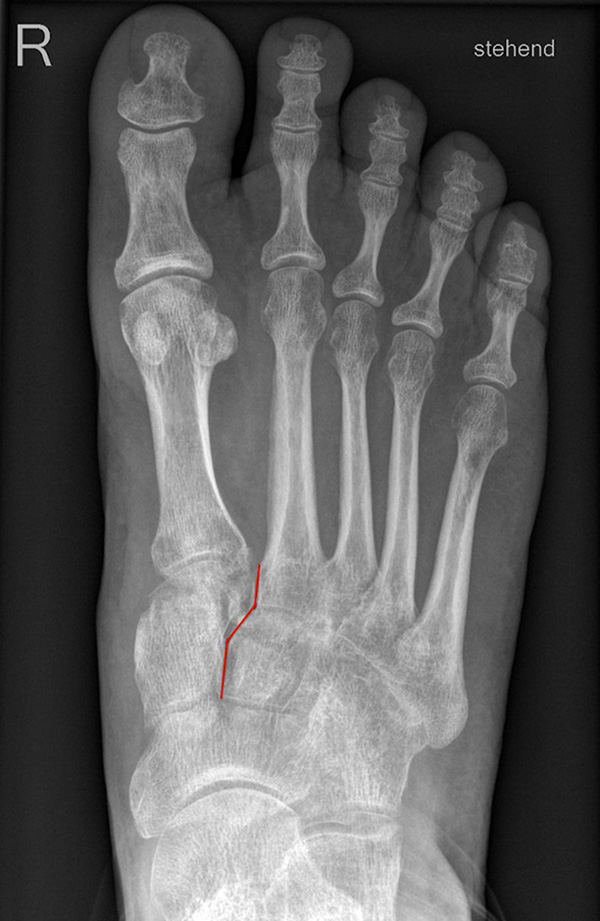

Auf den dp-Aufnahmen sollte der mediale Rand der Metatarsale-2-Basis mit dem medialen Rand des Os cuneiforme intermedium eine homogene Linie ohne Stufenbildung bilden (Abb. 7+8). Außerdem ist auf den Abstand zwischen der Metatarsale-1- und -2-Basis zu achten. Dieser sollte nicht größer als 2 mm bzw. im Vergleich zur Gegenseite nicht mehr als 1 mm erweitert sein. In bis zu 90% der Fälle zeigt sich ein sogenanntes „Fleck sign“ (Abb. 9), ein knöchernes Fragment zwischen der Metararsale-1- und -2-Basis im Sinne eines knöchernen Ausrisses des Lisfranc-Ligaments an der Metatarsale-2-Basis 211936410. Oft liegen zusätzliche Frakturen der Metatarsalebasen oder der Tarsale vor, die ebenfalls identifiziert werden sollten. Bei jeder Mittelfußbasisfraktur sollte umgekehrt an eine Lisfranc-Verletzung gedacht werden.

Zum Lesen der Bildbeschreibung und zur Vollansicht bitte die Bilder anklicken.